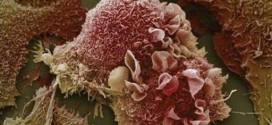

Leer MásCÁNCER DE PULMÓN NO MICROCÍTICO (CPNM)

El cáncer de pulmón no microcítico (CPNM). Los pulmones son dos órganos con apariencia de esponja que se encuentran en su pecho. El pulmón derecho se divide en tres secciones, denominadas lóbulos. Su pulmón izquierdo tiene dos lóbulos. El pulmón izquierdo es más pequeño debido a que el corazón ocupa más espacio en ese lado del cuerpo. Cuando usted respira, …